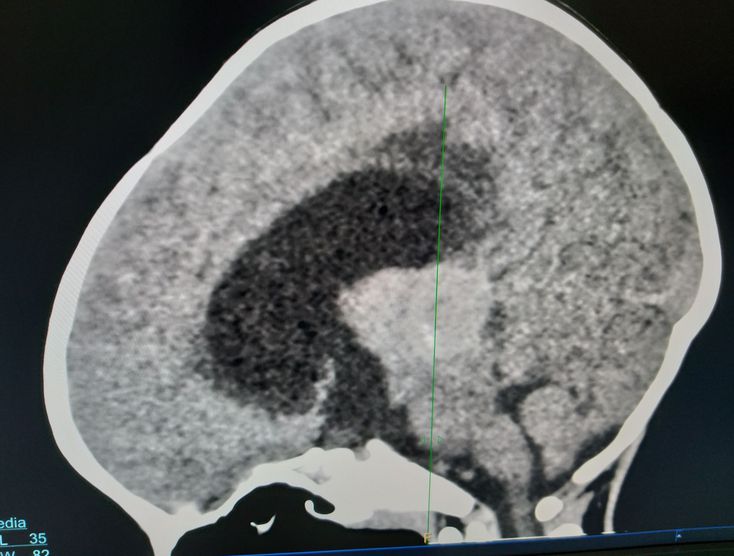

Hiperechogenic brain

Hiperechogenic brain tumor

Child

Seizure

Altered

Concience